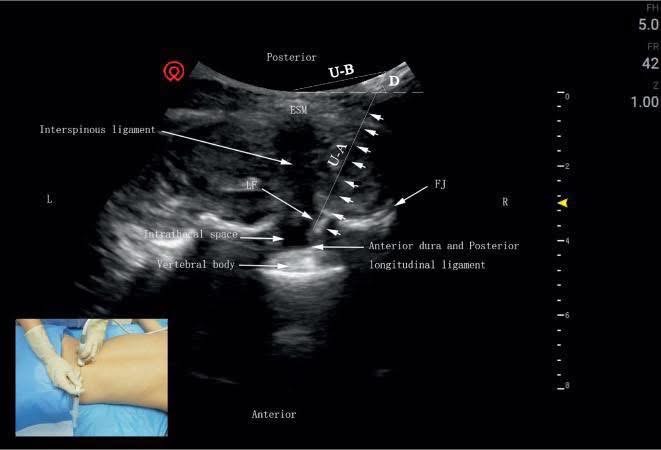

當別人在猜測病灶位置時,我們已經透過精準的影像報告鎖定目標;當別人在「盲目」嘗試時,我已經引進了超音波導引輔助技術,讓針尖在精密顯像下精準定位。

對我來說,解剖結構早已在腦海中 3D 全彩建模,再加上數位影像的實時護航,這不是盲目,而是「極致的精準」